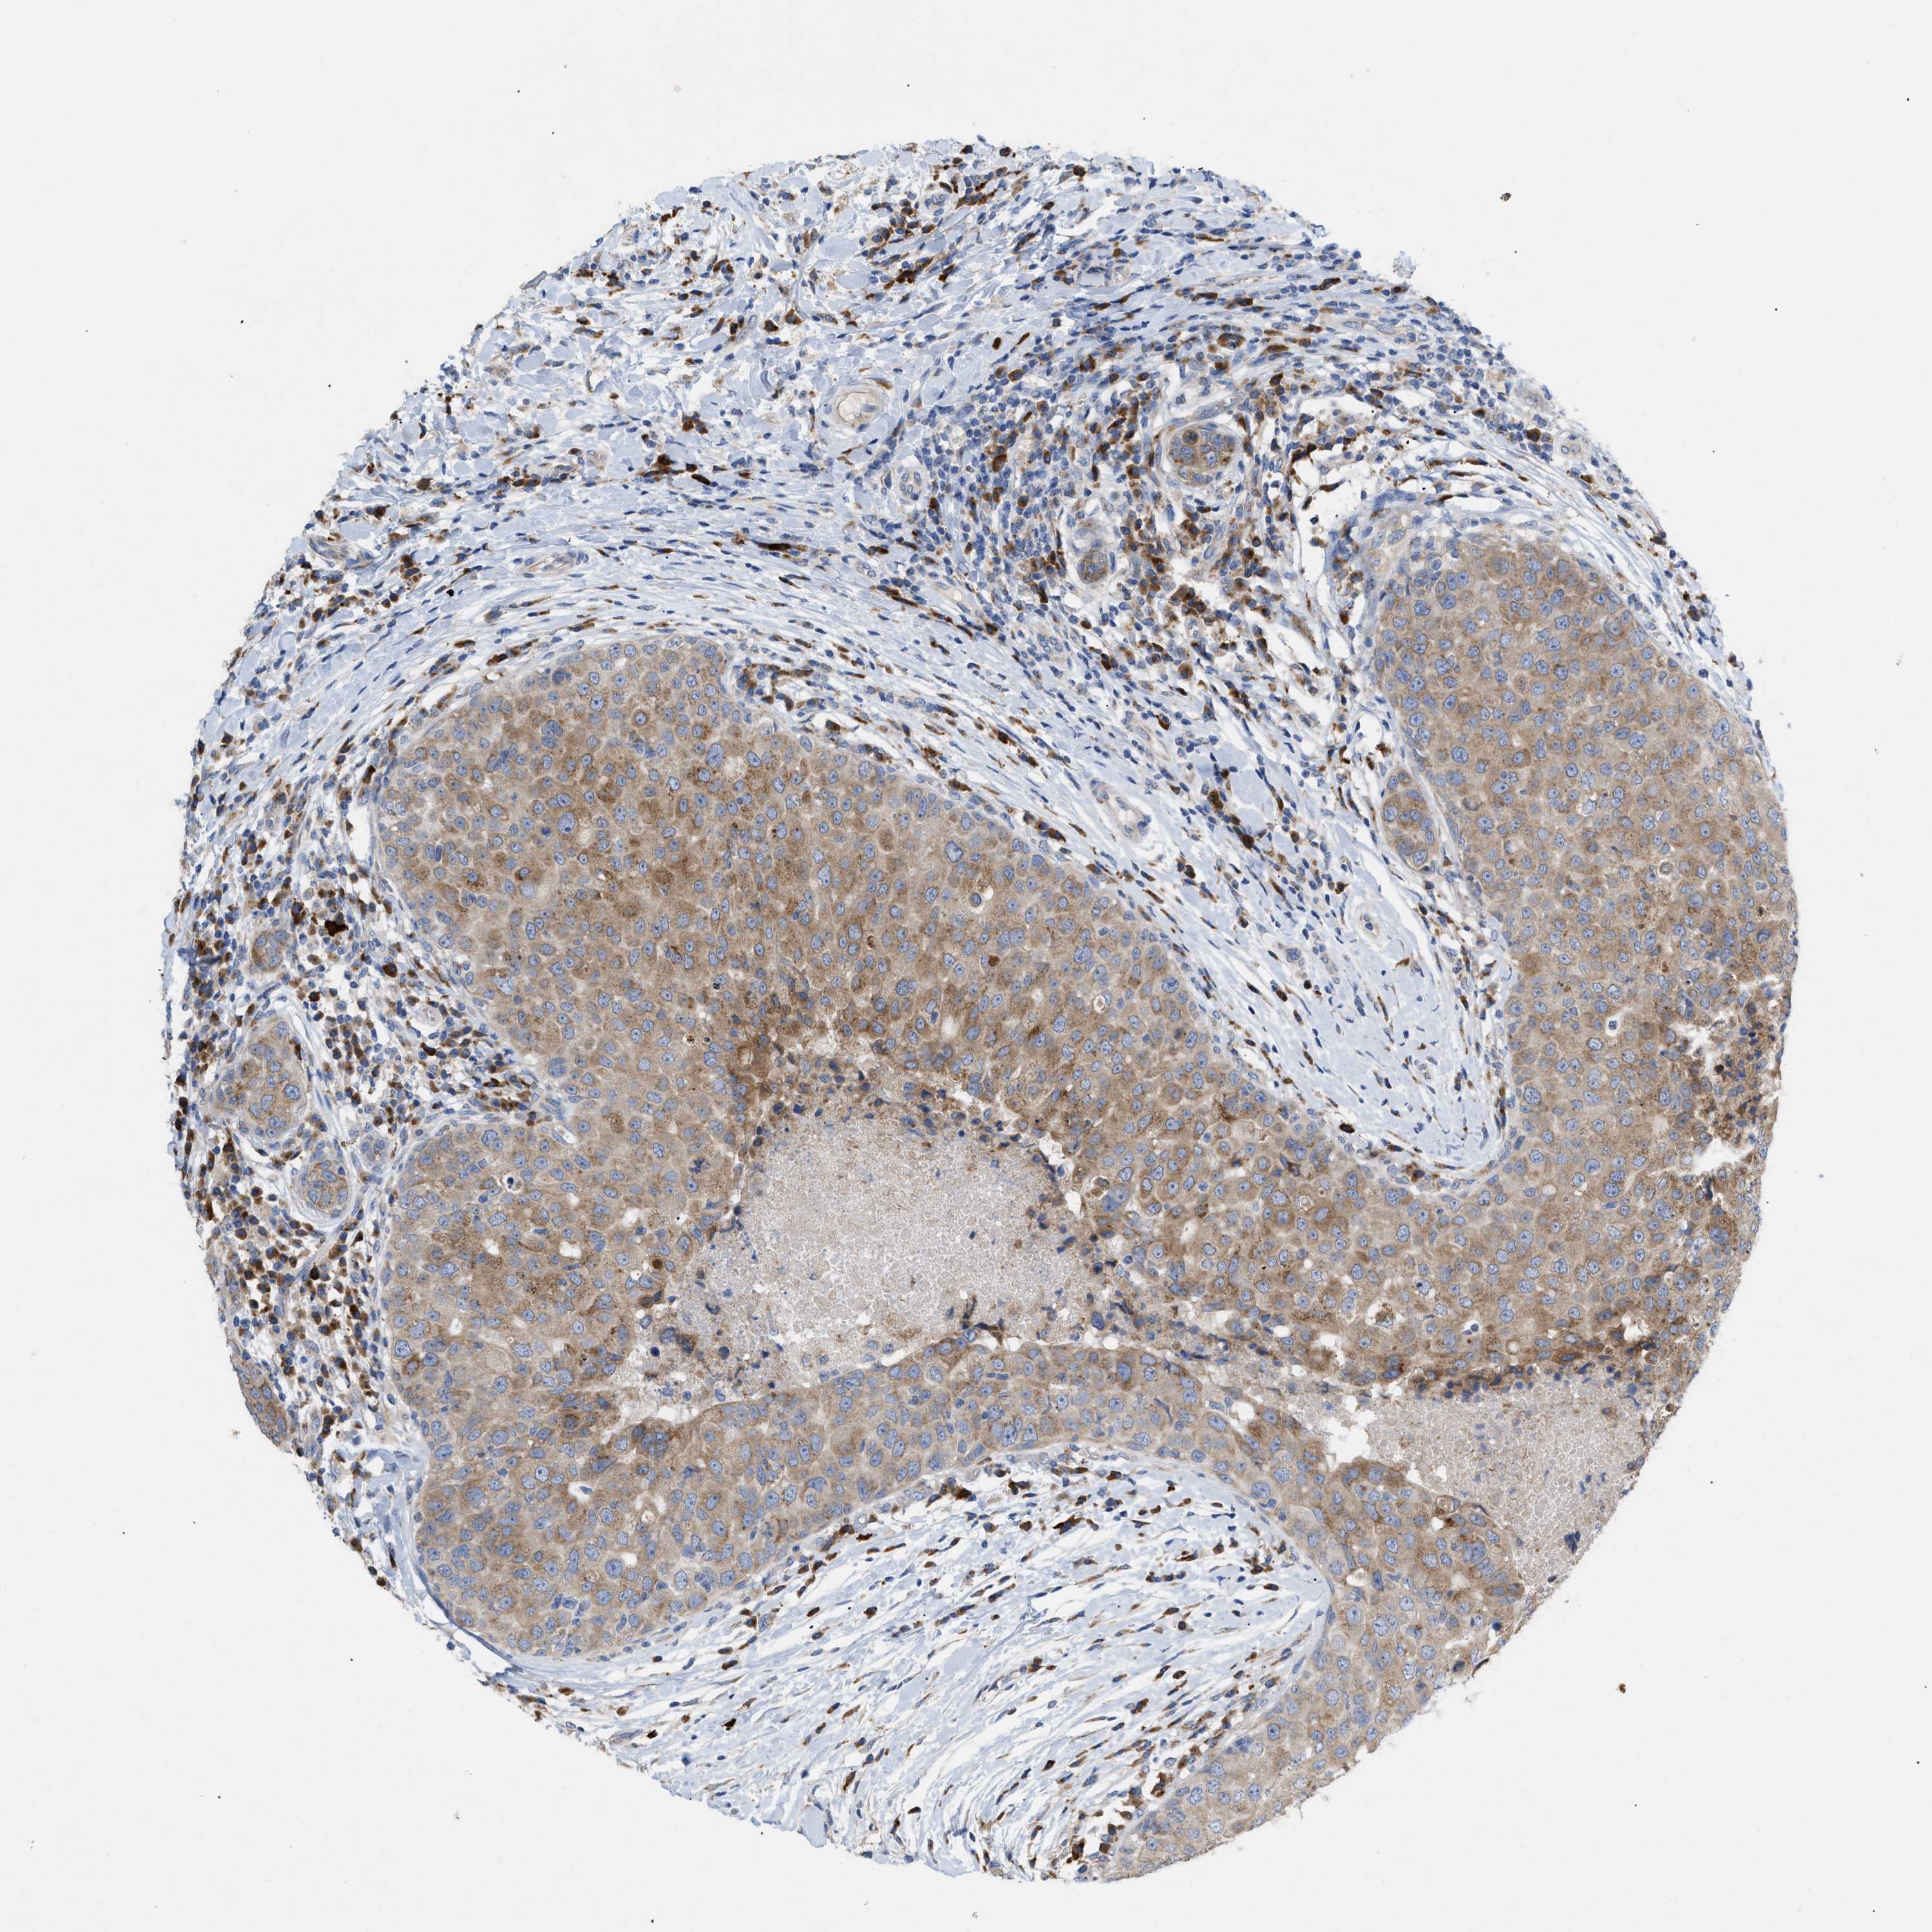

BRCA TCGA BRCA VALIDATION PROTEIN EXPRESSION

ANTIBODIES

AND

VALIDATION